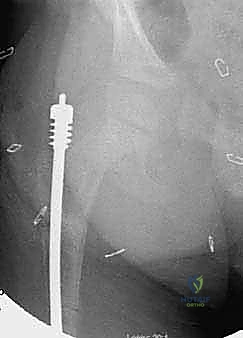

الدليل التفصيلي لخطوات العملية الجراحية: بضع العظم عبر الجلد والمسامير التلسكوبية

تُعد هذه العملية من أدق العمليات في جراحة عظام الأطفال، وتتطلب مهارة استثنائية كما هو الحال مع البروفيسور محمد هطيف. يتكون المسمار التلسكوبي (Fassier-Duval) من جزأين يتداخلان ببعضهما البعض (مثل التلسكوب). يتم تثبيت أحد الأطراف في أعلى العظم والطرف الآخر في أسفله. عندما ينمو العظم، ينزلق الجزء الداخلي من المسمار للخارج، مما يسمح للعظم بالنمو الطبيعي دون أن ينثني أو ينكسر.

الخطوة الأولى: التخطيط الجراحي الدقيق (Pre-operative Planning)

قبل العملية، يقوم الدكتور هطيف بإجراء دراسة شاملة لصور الأشعة السينية (X-rays) المأخوذة بدقة، لحساب زوايا التقوس بدقة متناهية، وتحديد نقاط بضع العظم (أماكن القص)، واختيار الحجم والطول المناسبين للمسمار التلسكوبي.

الخطوة الرابعة: إدخال المسمار التلسكوبي

بعد تقويم العظم وجعله مستقيماً كحبات المسبحة على خيط، يتم إدخال السلك الدليلي (Guide Wire). ثم يتم إدخال الجزء الخارجي (الأنثوي) من المسمار التلسكوبي وتثبيته في الجزء العلوي من العظم (Epiphysis).

بعد ذلك، يتم إدخال الجزء الداخلي (الذكري) من المسمار عبر الجزء السفلي من العظم وتثبيته في المشاشة السفلية. هذا التصميم العبقري يضمن حماية العظم بالكامل من الداخل.